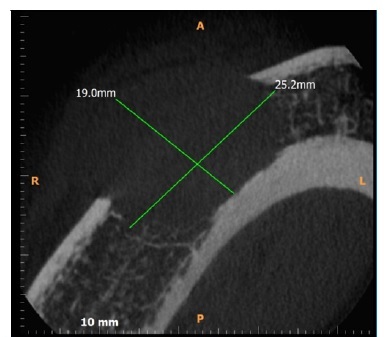

A TC (Figuras 1, 2 e 3) revelou imagem hipodensa, ostelítica, de forma ovalada, promovendo rompimento da cortical vestibular, envolvendo o ápice dos dentes 44 e 45. Nesse momento, a paciente informou ter o diagnóstico de mieloma múltiplo há sete anos, sendo acompanhada por hematologista, sem apresentar sinais clínicos da manifestação da doença.

Figura 1 Reconstrucao axial de TC, evidenciando lesão hipodensa, osteolitica, causando rompimento da cortical vestibular e medindo 19 mm x 25 mm.